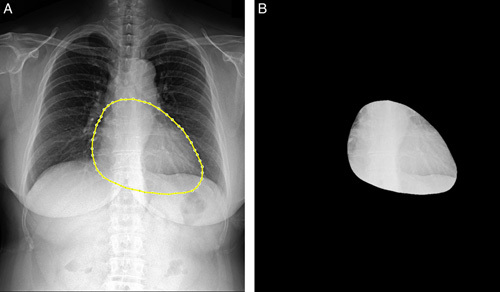

Materials and methods: We included 559 patients who underwent a CAC scan with CXR obtained within 6 months and divided them into training (n = 391) and validation (n = 168) cohorts. We extracted radiomic features from annotated cardiac contours in the CXR images and developed an RS through feature selection with the least absolute shrinkage and selection operator regression in the training cohort. We evaluated the incremental value of the RS in predicting CAC scores when combined with basic clinical factor in the validation cohort. To predict a CAC score ≥100, we built an RS-based machine learning model using random forest; the input variables were age, sex, body mass index, and RS.

Abstract Image